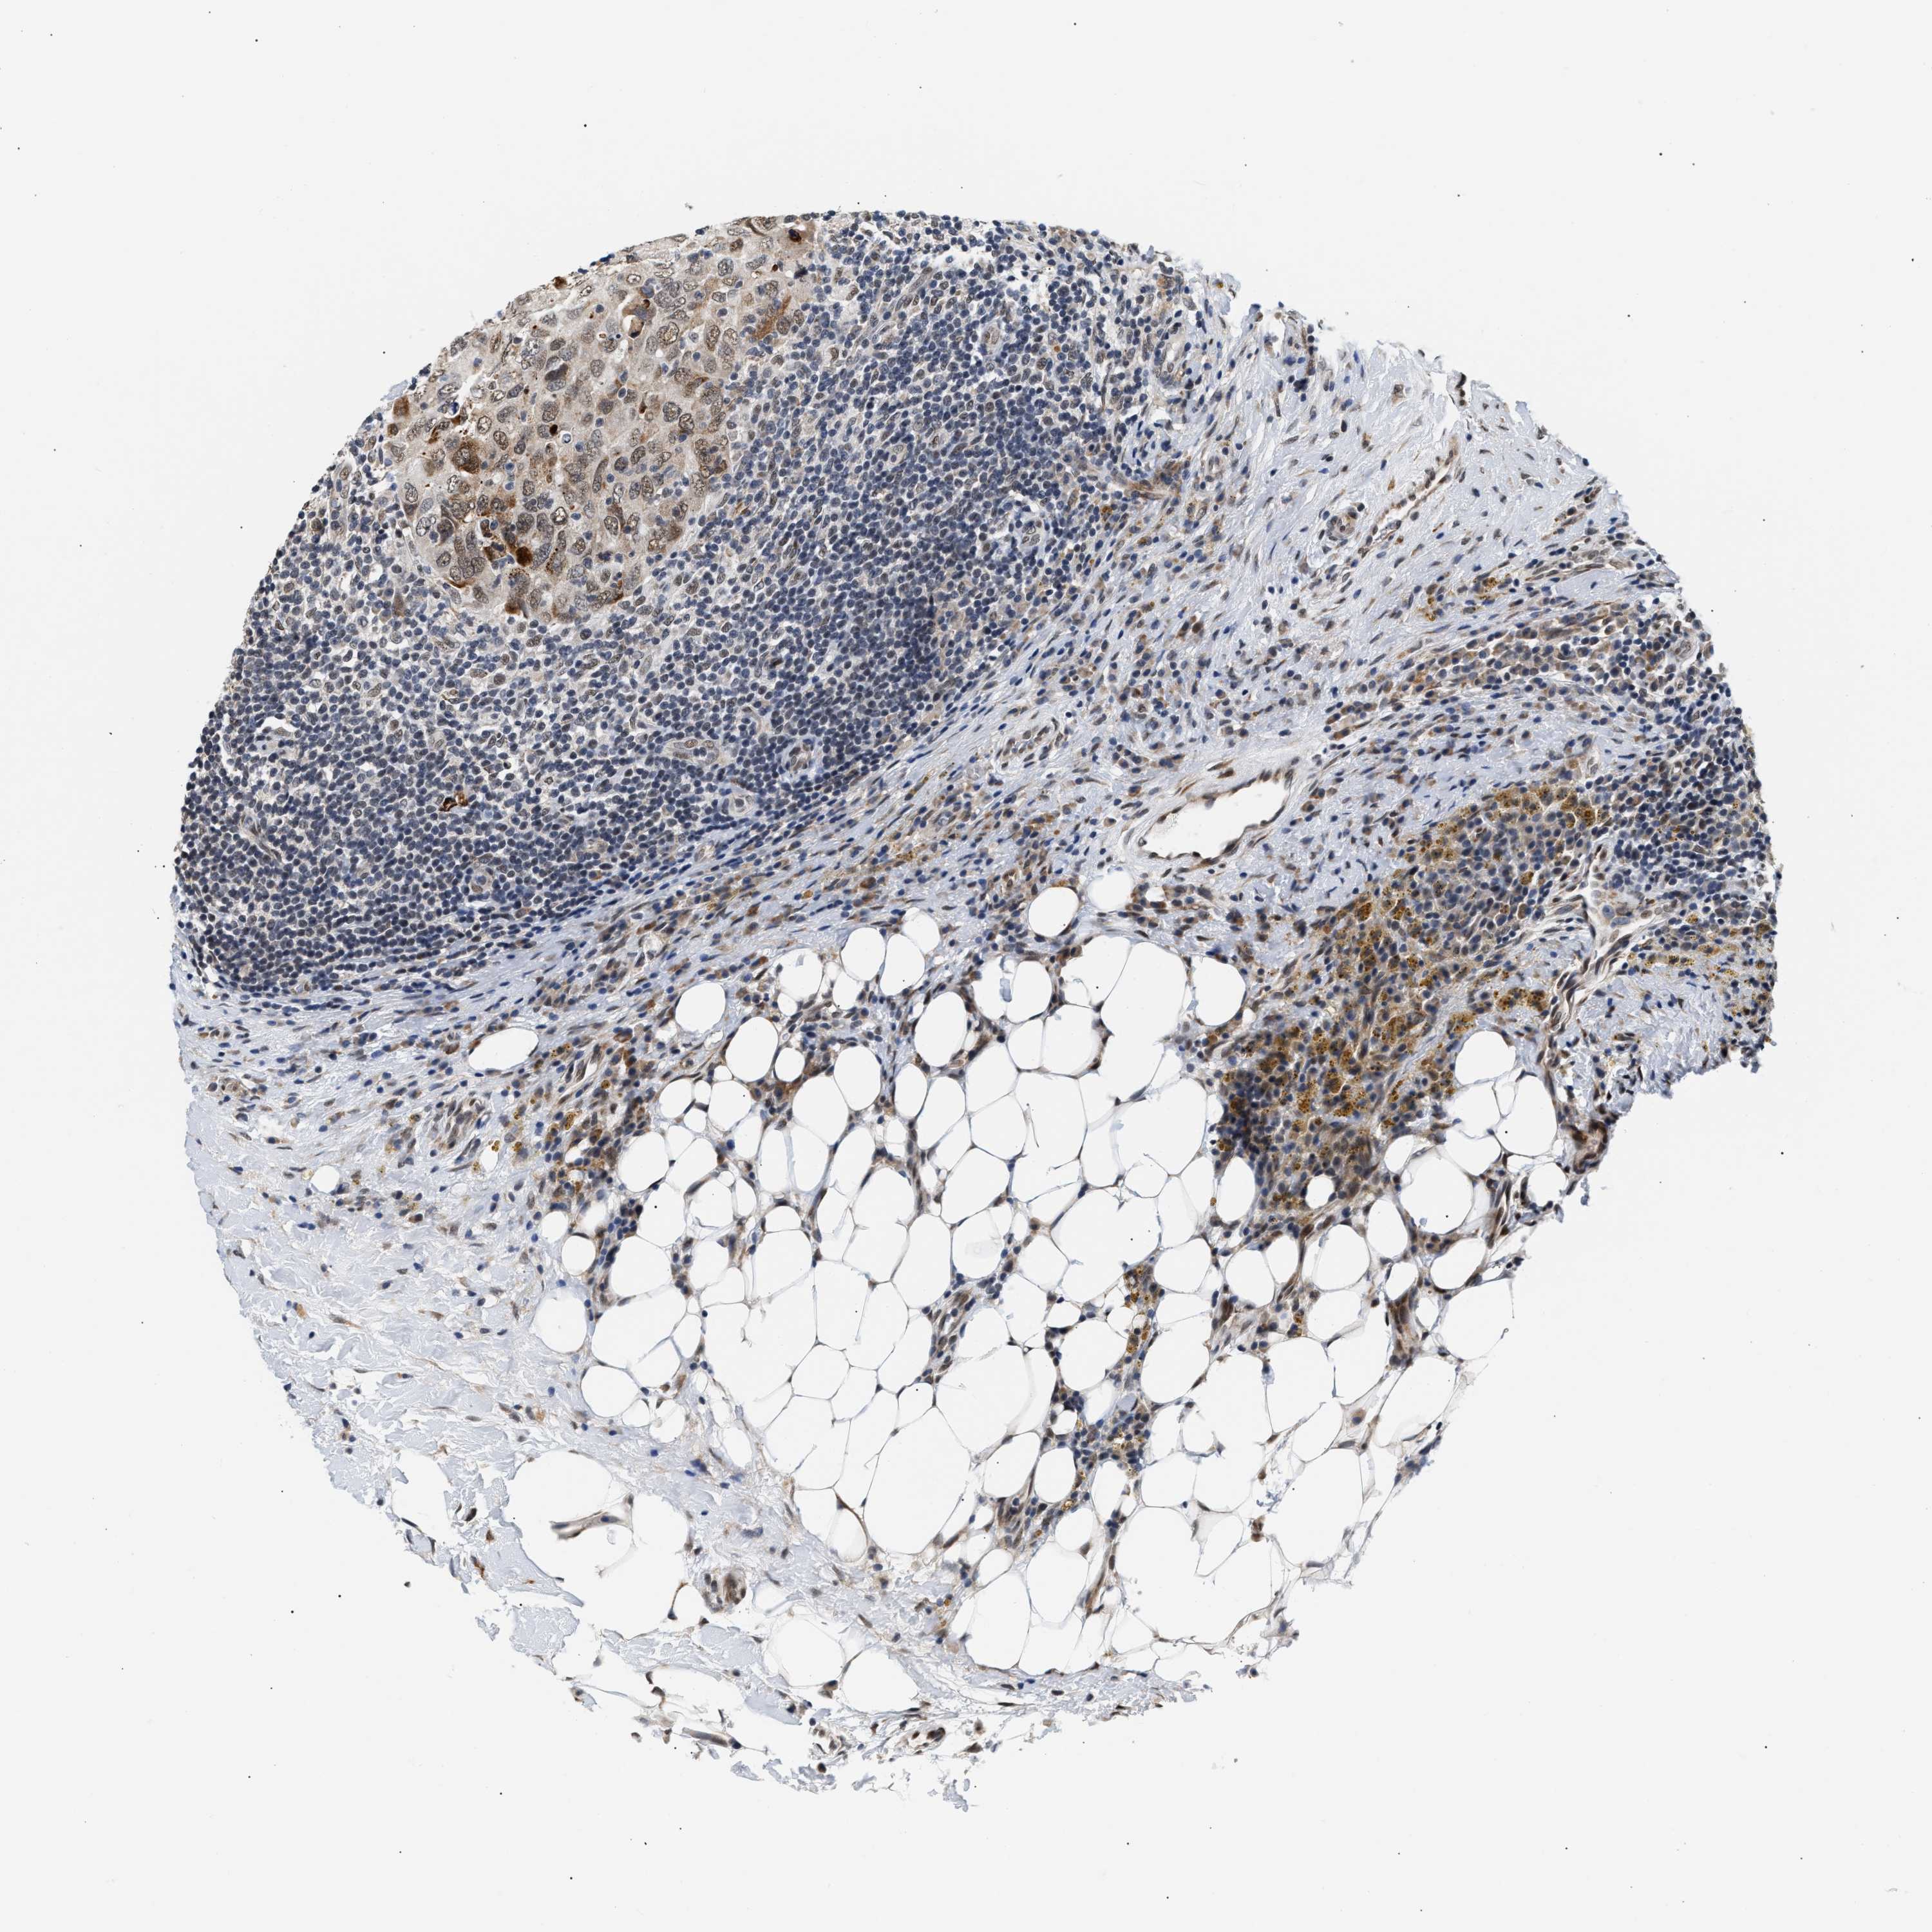

CANCER BREAST CANCER Show tissue menu

BRCA TCGA BRCA VALIDATION PROTEIN EXPRESSION